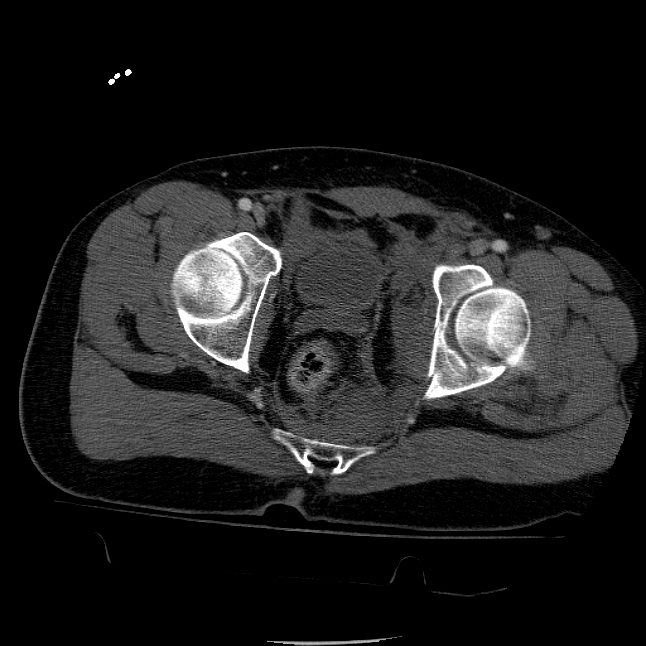

25 yo brittle diabetic, became hypoglycemic and passed out on his motorcycle. Sustained bilateral lateral Hoffa fractures with associated LCL injury on the right and right distal radius fracture. I have questions regarding his pelvic ring/acetabular fracture on the left. Appears to be a very low posterior column fracture with associated posterior wall, marginal impaction. Superior and inferior rami fractures as well on the left giving him a floating segment of inf ramus/ischium/posterior column, but no detectable posterior ring injury. Should the posterior column/posterior wall fracture be addressed surgically because of the marginal impaction? Or is this fracture low enough to be treated non-operatively? I appreciate the input.

It's an interesting case. The plain films show the impaction, but most of the joint looks pretty good. The CT cuts look awful, though.

The impaction is so big I don't think I would ignore it. It IS down low, but it takes up almost the whole southern hemisphere of his joint.